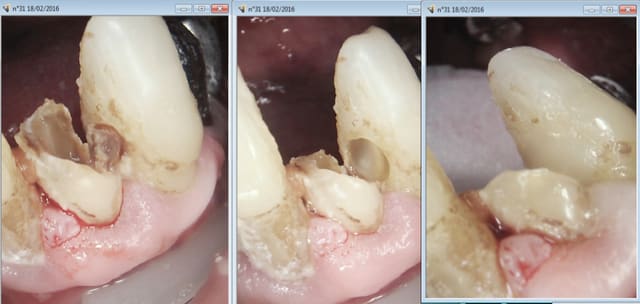

Exemple

Je compte la pré op de 32 à part ( dans le cadre d'un status justifié par des antécédents de soins intensifs )

Je ne sais pas lors du cliché préop si ca va se terminer en extraction ou en endo.

Finalement je fais l'endo car j'estime que je peux réhabiliter cette dent.

Je compte le jour de l'endo un HBQK040.

Ceci dit j'ai fait une erreur : la radio cone scellé n'est pas une radio finale. le cone devrait etre coupé ou condensé au mac spadden. Cette radio n'est donc pas valable. ( je te rassure c'est un oubli extrêmement rare chez moi)

La 33 je n'étais pas sur de la garder vivante et de ne pas faire une endo non plus. Je n'en suis toujours pas sur d'ailleurs le patient étant revenu consulter pour une douleur dans le secteur 32 - 33( il n'avait pas voulu faire les soins lors du status ne consultant que pour un détartrage). Il a compris depuis ! -))))